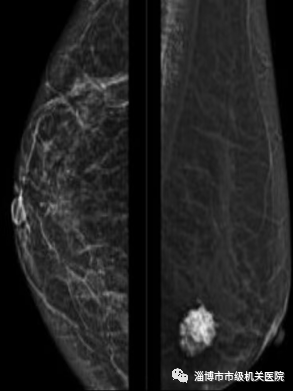

二、乳腺钼靶主要看钙化

钼靶的优势:钼靶对发现微小钙化最具有优势,进而能够发现无症状或触摸不到的肿瘤,诊断效率非常高。

1. 钼靶需将整个乳房压紧,如果患者乳腺腺体丰富,腺体会与病变重叠在一起,于是难以辨别是腺体还是病变,同时会有一定的压痛。